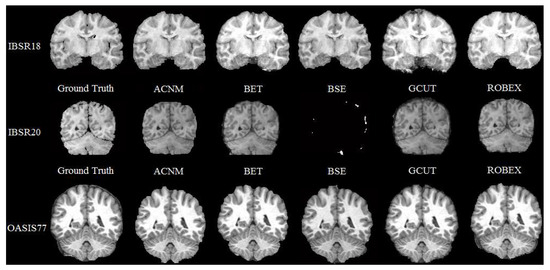

3.2. Comparison to Other Methods